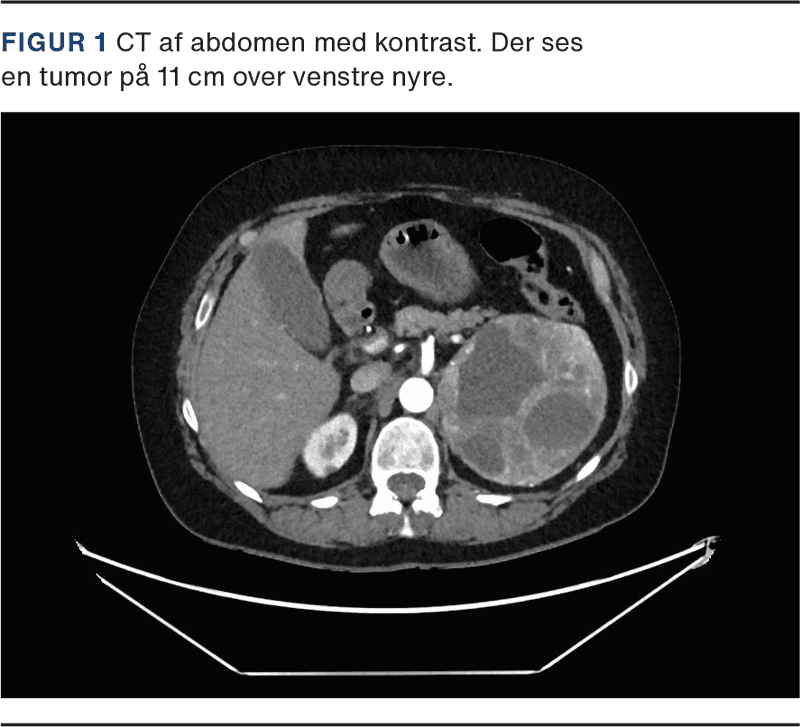

Patienten visiteredes til intensiv terapi, hvor hun udviklede tiltagende multiorganpåvirkning med sløret sensorium, respirationsinsufficiens, cirkulatorisk svigt og vigende diureser. Ekkokardiografi viste svært nedsat venstre ventrikel-uddrivningsfraktion (LVEF) 20% uden tegn til højresidig belastning. CT af thorax og abdomen var uden lungeemboli. Som bifund fandtes en 11 cm stor tumor over venstre nyre (Figur 1). Efterfølgende blodprøver viste massivt forhøjede værdier af 3-methoxyadrenalin 452,5 nmol/l (referenceniveau: < 0,47 nmol/l [2]) og 3-methoxynoradrenalin 203,5 nmol/l (referenceniveau: < 1,10 nmol/l). Der kræves ingen patientforberedelse forud for prøvetagning [2].